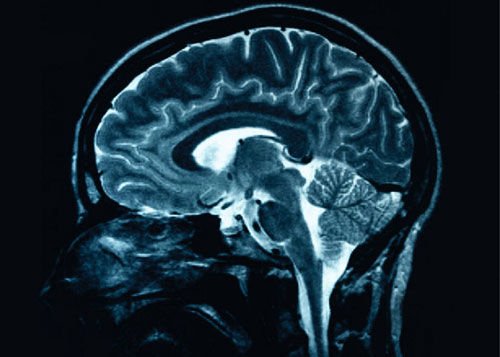

人的大脑是人体中最微妙的智能器官。人脑和动物脑有着很大的不同,虽然从解剖学上看并无太大区别。首先,与其它几乎所有的动物相比,从大脑在体重中所占的比率来看,人类的大脑是比较大的;其次,人脑虽然只有1.5kg,但是却由140亿个神经元组成,极其复杂细致;第三,人类大脑的结构也远远比其它动物的复杂,大脑成比例地拥有更多的与处理更高级的脑功能相关的区域,例如认知与记忆。因为这些因素,在很大程度上使人类成为地球上的优势物种。与其他动物不同,灵长类动物和人类有一个非常庞大和发达的大脑皮质,这对进化非常重要。人类有些高级智力行为是由这个皮层区域控制的,包括意识,语言等能力。据悉,人脑从内侧往外分原皮质、旧皮质、新皮质三大部分。原皮质起着爬虫类脑的作用,旧皮质起着哺乳类脑的作用,原皮质和旧皮质与嗅觉和内脏活动有关;惟有人类有别于其它动物的新皮质特别发达,占大脑半球皮质的96%以上,是多极神经元集中的部位,成为机体各种生命活动的最高调节器,新皮质是用来学习知识和进行精神活动的。而研究发现,大脑的高级神经活动可能与新皮质的厚度有密切关系,新皮质越厚,人的智商越高。

这项研究是由加州大学旧金山分校的一组研究人员负责。研究人员注意到,大脑中有一类新发现的干细胞可以在很大程度上帮助新皮质的形成。该校的神经生物学家阿诺德·克雷格斯坦(Arnold Kriegstein)指出,新型干细胞很有可能也存在于猫等哺乳动物大脑中,不过,在灵长类动物和人类大脑中这种干细胞会更活跃,数量也更多。因此,当这些干细胞向神经元发展,就成为大脑中“电信号”的主要渠道,理所当然地,原始细胞转化为越来越多的神经细胞,因此形成了更厚的新皮质。 随着干细胞研究领域向深度和广度不断扩展,人类的大脑有望变得更大,未来的人将变得更聪明。